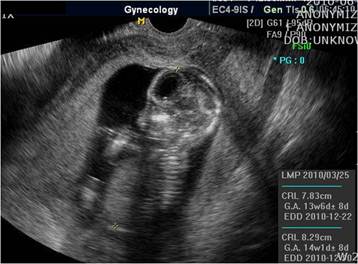

At the time of laparoscopy, 800 ml of fresh blood and 0.5-cm fundal defect of the uterus were noted (Fig. 2). The placenta and amniotic membrane were seen bulging spontaneously and slowly, and the uterine defect was gradually enlarging, with its size increased to 3 cm as last noted. Because the amount of blood in the ruptured area increased rapidly, we decided to convert laparoscopy to laparotomy. At the beginning of the laparotomy, the fetus was spontaneously delivered through the ruptured site. We preferred total abdominal hysterectomy to conservative management because of the large, fragile, and thin uterine wall with abundant blood vessels on the surface. The total estimated blood loss during the operation was 1000 ml; the patient was transfused 4 units of packed red blood cells and 2 units of fresh frozen plasma. Her recovery was uneventful, and she was discharged on postoperative day 6. The final pathological examination revealed that the chorionic villi had invaded the entire myometrium up to the serosa, confirming the diagnosis of placenta percreta (Fig. 3). The length of the fetus measured from the crown to rump was 9.0 cm, and fetal weight was 69.3 g; these measurements were consistent with 14 weeks of gestation.

Figure 2

Ruptured uterus and bulging amnion and placenta enlarging the ruptured hole. arrow: uterine fundus; arrow head: amnion and placenta.